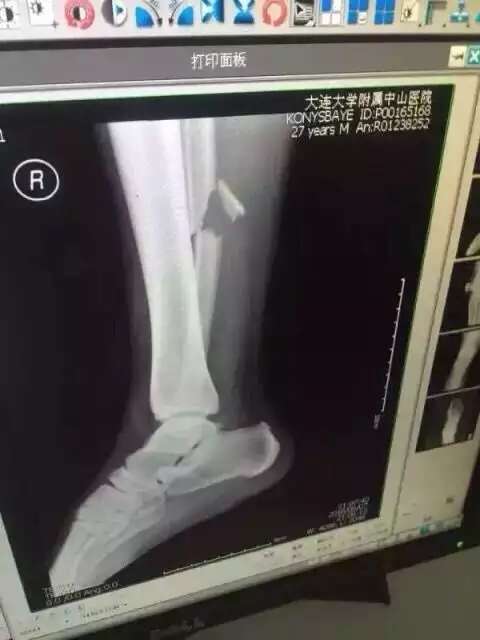

Полузащитник сборной Китая Жэнь Хан принес извинения за травму, которую он нанес игроку сборной Казахстана Улану Конысбаеву, сообщает Vesti.kz.

Инцидент случился на 45-й минуте матча, который проходил в Даляне. За него Хан получил предупреждение, а Конысбаев в результате инцидента получил ужасную травму. Прямо с поля полузащитник был увезен на машине "скорой помощи" в больницу, где ему сделали операцию.

Фото со страницы пользователя Facebook Сержана Касена